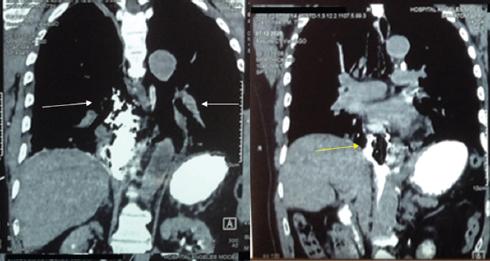

En la exploración física el paciente se encuentra despierto, escala de Glasgow 15 puntos, facies álgica, polipneico, con enfisema subcutáneo en la región supraclavicular y el tórax superior bilateral con crepitación, sin equimosis, con requerimiento de oxígeno suplementario por puntas nasales a 5 l/min, con disminución del murmullo vesicular en la región basal del hemitórax derecho y dolor abdominal a la palpación superficial y profunda en la región epigástrica, así como intolerancia al decúbito supino. El resto de la exploración no mostraba alteraciones, con los siguientes signos vitales: presión arterial 130/80 mmHg, frecuencia cardiaca 100 latidos por minuto, frecuencia respiratoria 20 respiraciones por minuto, temperatura 36.6 °C, saturación de oxígeno 96% y fracción inspirada de oxígeno 30%. Los parámetros de laboratorio fueron: hemoglobina 15.7 g/dl, hematocrito 45.9%, leucocitos 12.3 × 103/ml, glucosa 128 mg/dl, procalcitonina 34 ng/ml y troponina I < 0,04 ng/ml. El electrocardiograma mostró ritmo sinusal, frecuencia cardiaca 97 latidos por minuto, AQRS 0°, QRS 0.12 s y sin alteraciones del segmento ST. Se decidió realizar una radiografía de tórax, en la que se observó un enfisema subcutáneo en la región supraclavicular y ensanchamiento del mediastino (Fig. 1), y una tomografía computarizada de tórax con medio de contraste oral hidrosoluble, que confirmó el enfisema subcutáneo con extensión hasta la región escapular bilateral. También se observó neumomediastino bilateral, neumopericardio y fuga del medio de contraste hidrosoluble a nivel del tercio inferior del esófago hacia el mediastino medio, la cavidad pleural y el pericardio (Figs. 2 a 4). Se inició antibioticoterapia intravenosa (betalactámico y clindamicina).

Figura 2 Tomografía computarizada de tórax, ventana para mediastino (corte coronal), con medio de contraste hidrosoluble, en la que se observa neumomediastino bilateral de predominio a nivel medio y posterior (flechas blancas), el cual no desplaza ni comprime las estructuras adyacentes. Se observa neumopericardio (flecha amarilla).